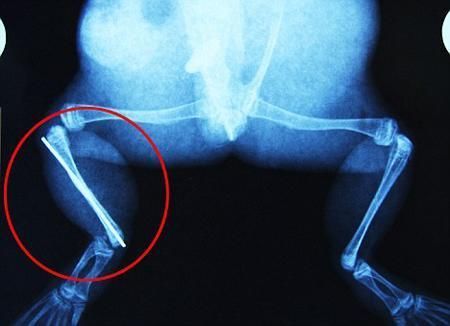

環(huán)球網(wǎng)4月2日報道 據(jù)《每日郵報》報道,上個月,南非大牛蛙布魯萊的右小腿被鄰居家的一只狗咬到,導(dǎo)致粉碎性骨折,現(xiàn)在經(jīng)過2個小時的手術(shù),它的斷腿已經(jīng)被接上,它也因此成為有史以來第一只通過外科手術(shù)用鋼針接上斷腿的青蛙。

野生生物專家安妮經(jīng)常為學(xué)校寫教材,她認(rèn)為這是人類第一次通過手術(shù)給一只青蛙接斷腿。在手術(shù)開始階段,獸醫(yī)把少量給狗用的麻醉藥注入到這只青蛙體內(nèi),讓它失去知覺。然后他在布魯萊的斷腿上切開一個小口,把一根小鋼針植入腿里。最后獸醫(yī)給它縫了9針,把切口縫合在一起。僅僅幾周后,布魯萊就能在安妮家附近活動了。這只青蛙大約已有25歲,主要以嚙齒動物、蛇和其他青蛙為食。布魯萊所屬的牛蛙種群正在不斷減小,目前只能在非洲南部的濕地里才能看到這種青蛙。

安妮有2個孩子,她已經(jīng)從事20多年兩棲動物保護(hù)工作。她認(rèn)為鄰居家的狗狗在把布魯萊從地下刨出來的時候,它正在地下冬眠、她說:“世界上只有這個地區(qū)能看到這種牛蛙,這種青蛙現(xiàn)在變得越來越稀少。因為我從事野生生物保護(hù)工作,因此認(rèn)識很多兩棲動物專家,但是以前他們誰也沒見過這種事情。看到布魯萊越來越健康我非常開心。現(xiàn)在還需要一段時間,它的金屬腿和它的骨骼才能融為一體,那時布魯萊會跟以前一樣健康。我們認(rèn)為這個過程需要幾周時間,但是一旦它完全康復(fù),我希望把它放歸大自然,讓它重新回到它最鐘愛的濕地里!